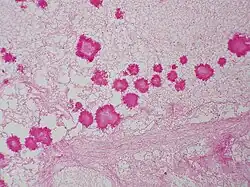

The diagnoses of geotrichosis cannot be determined without using culture or microscopic measurements.[5] The laboratory diagnosis of geotrichosis involves collected fungi samples areas of infections without contamination.[6] Scraping of the mouth lesions and the ulcers can provide a sample of G. candidum. Samples can also be collected from pus and mucus can be obtained from the feces.[5] Sputum can be searched for the mucoid-like white flakes for further examination.[6][5] Culturing the cylindrical barrel-shaped or elliptical fungi in considerable numbers in oral lesions is an indicator that a patient may have geotrichosis.[6] Under the microscope the fungi appears yeast-like and septate branching hyphae that can be broken down into chains or individual arthrospores. Arthrospores appear rectangular with flat or rounded ends.[3][5] Under the microscope the arthroconidia size range from 6-12μm x 3-6μm. Arthroconidia and coarse true hyphae can be observed can be observed under the microscope.[3] Another identification method for G. candidum is selective isolation method. A selection isolation method based on the fungi tolerance to novobiocin and carbon dioxide can determine if G. candidum is the cause of illness.[2]